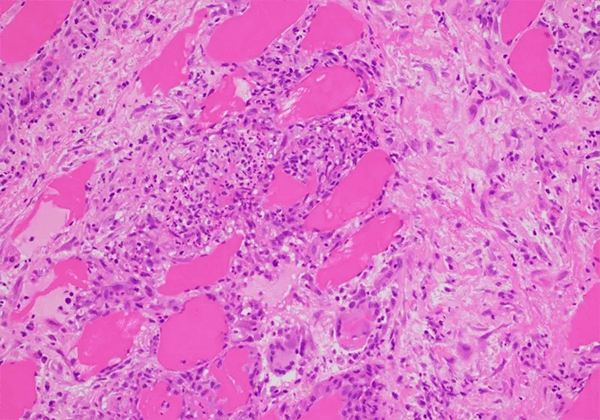

½á½Ú²¡ÊÇÒ»ÖÖ²¡Òò²»Ã÷µÄÂýÐÔ¶àϵͳÑ×ÐÔ¼²²¡£¬ÌØÕ÷Ϊ·Ç¸ÉÀÒÑùÉÏÆ¤ÑùÈâÑ¿Ö×£¬°éÓе¥¸öºËϸ°û½þÈóºÍ΢½á¹¹ÆÆË𡣸ò¡¿ÉÀÛ¼°Æ¤·ô£¬ÑÛ¾¦£¬ÐÄÔàºÍÖÐÊàÉñ¾ÏµÍ³£¬Áè¼Ý90%µÄ²¡ÀýÀÛ¼°·Î²¿¡£¸Ã¼²²¡ÊÇÖØ´óµÄ¡¢Î´Öª×ãµÄÒ½ÁÆÐèÇóÖ®Ò»¡£